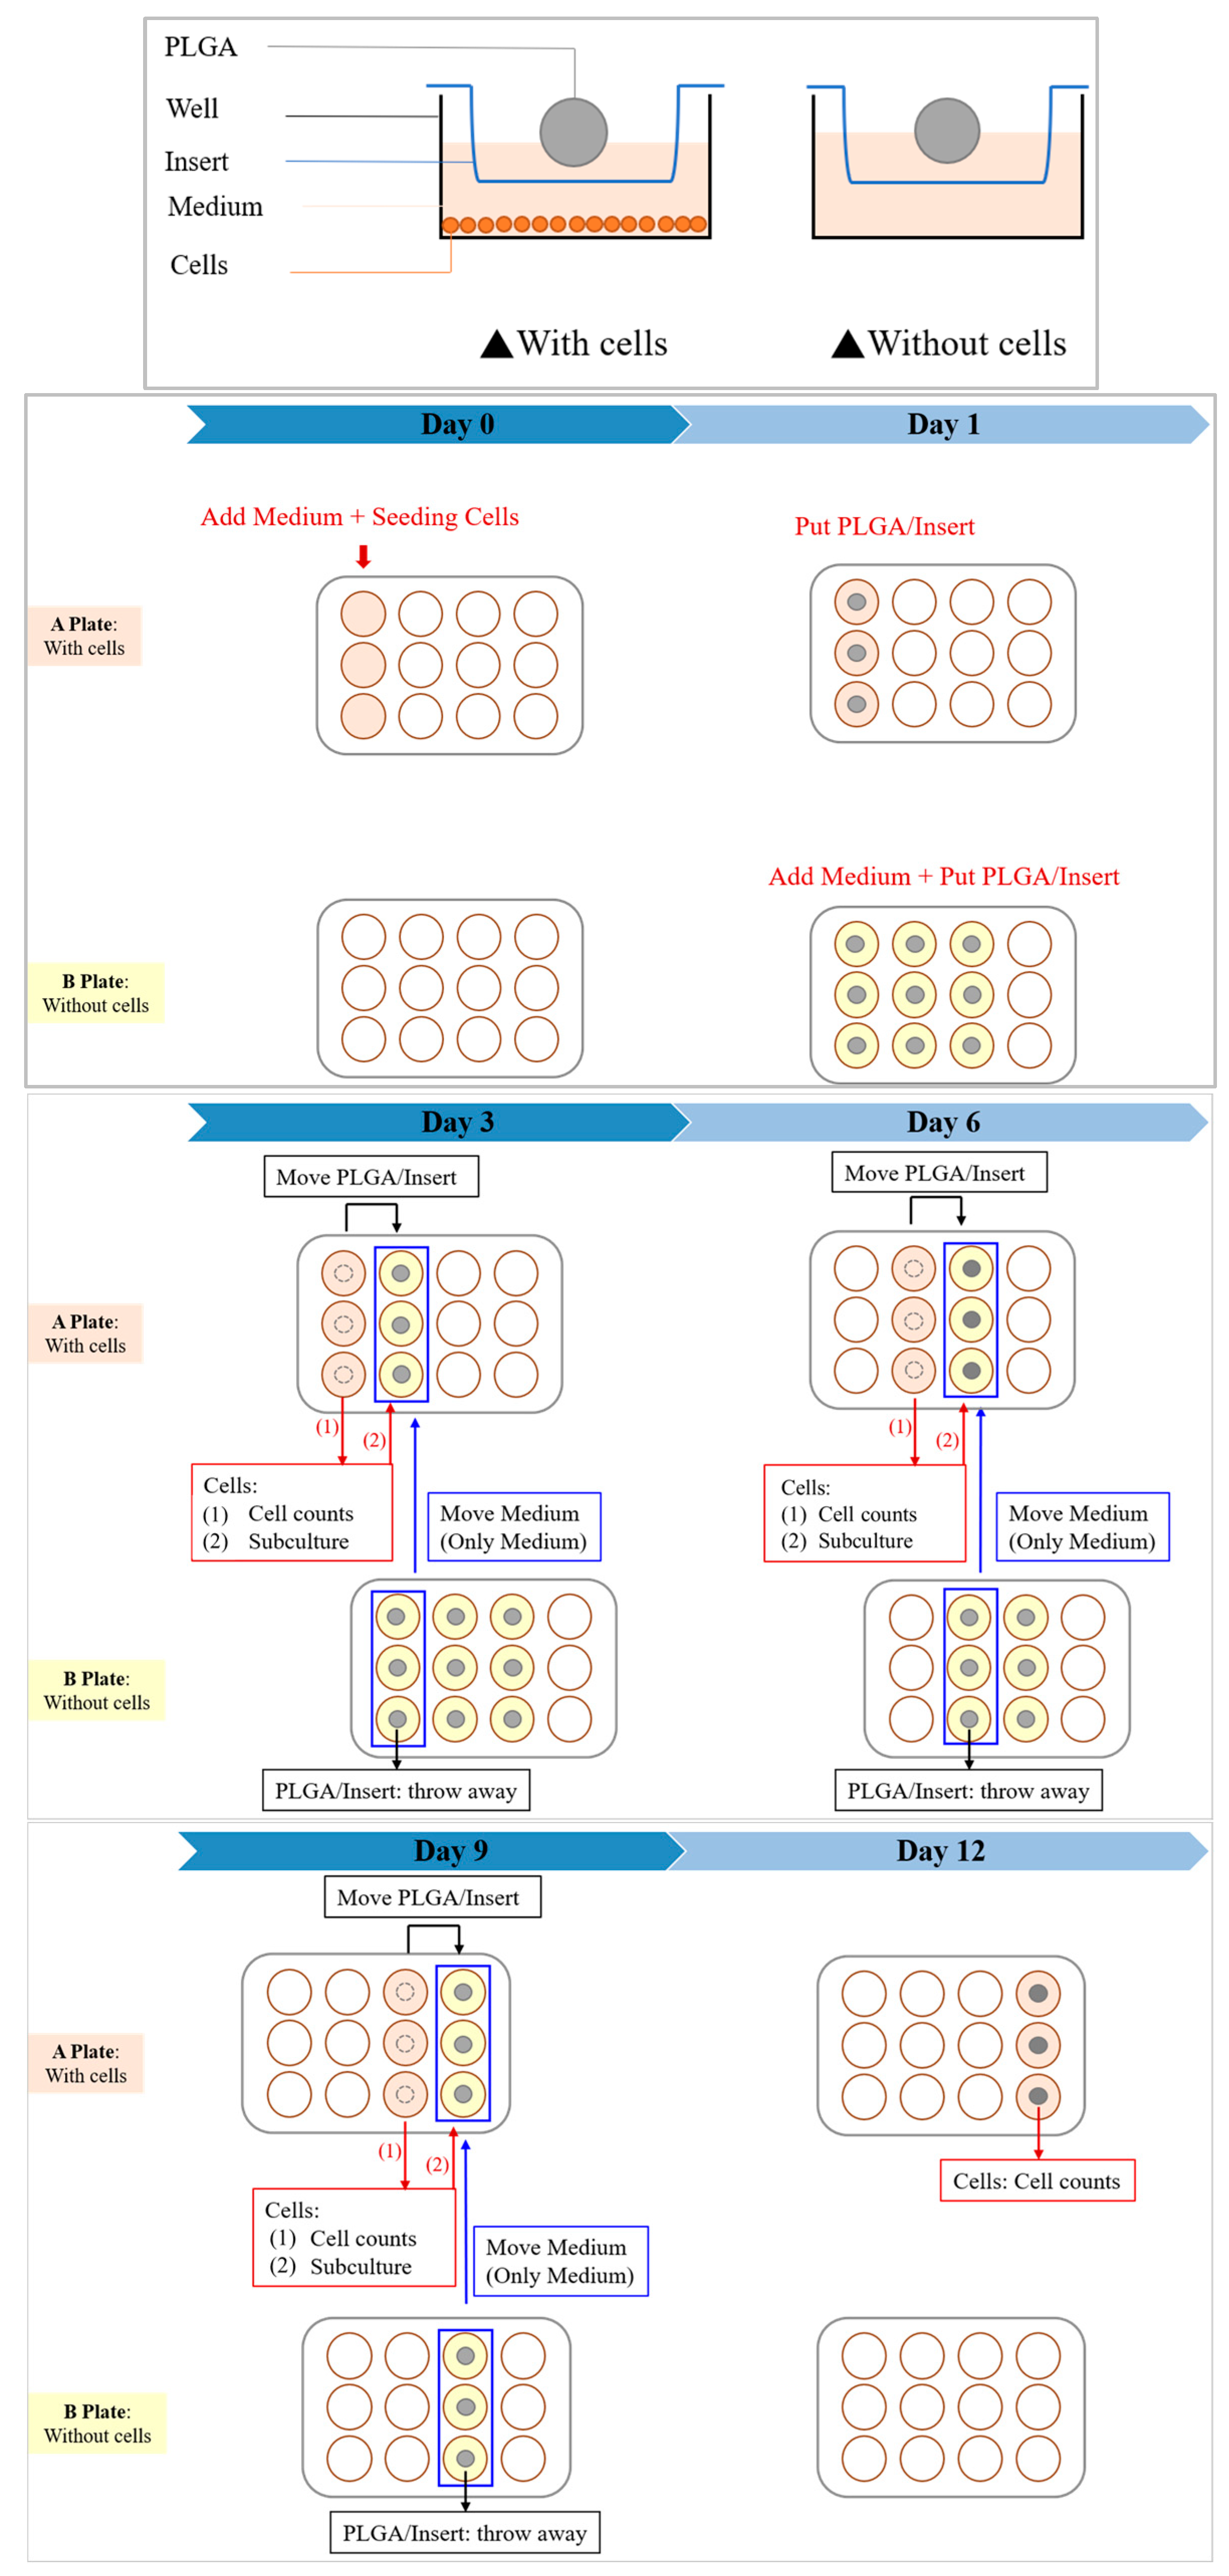

2.4. In Vitro Cytotoxicity Test

3.4. In Vitro Cytotoxicity Test